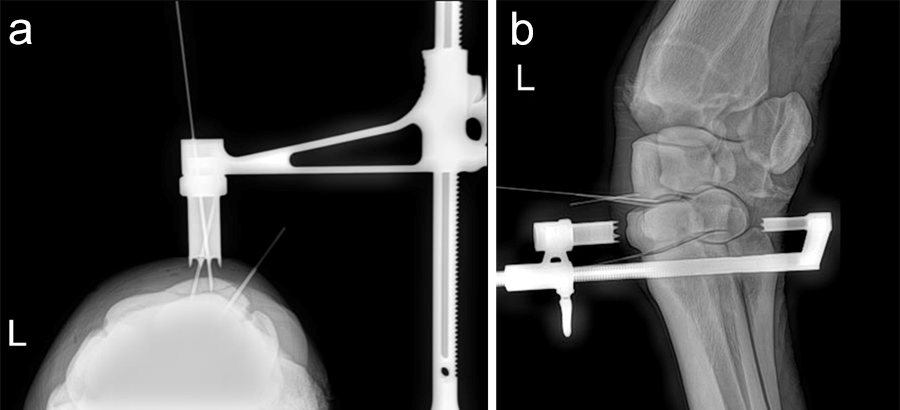

A frontal plane fracture of the third carpal bone was diagnosed at the track in this 3-year-old Thoroughbred racehorse, which was referred for surgery. Internal fixation was planned with a 3.5 mm cortex screw in lag fashion. The Screw Targeting Clamp (STC) placement was guided using needles with radiographic and arthroscopic imaging. From skin incision to screw placement, lag screw fixation was achieved through the STC without movement or removal of the device.